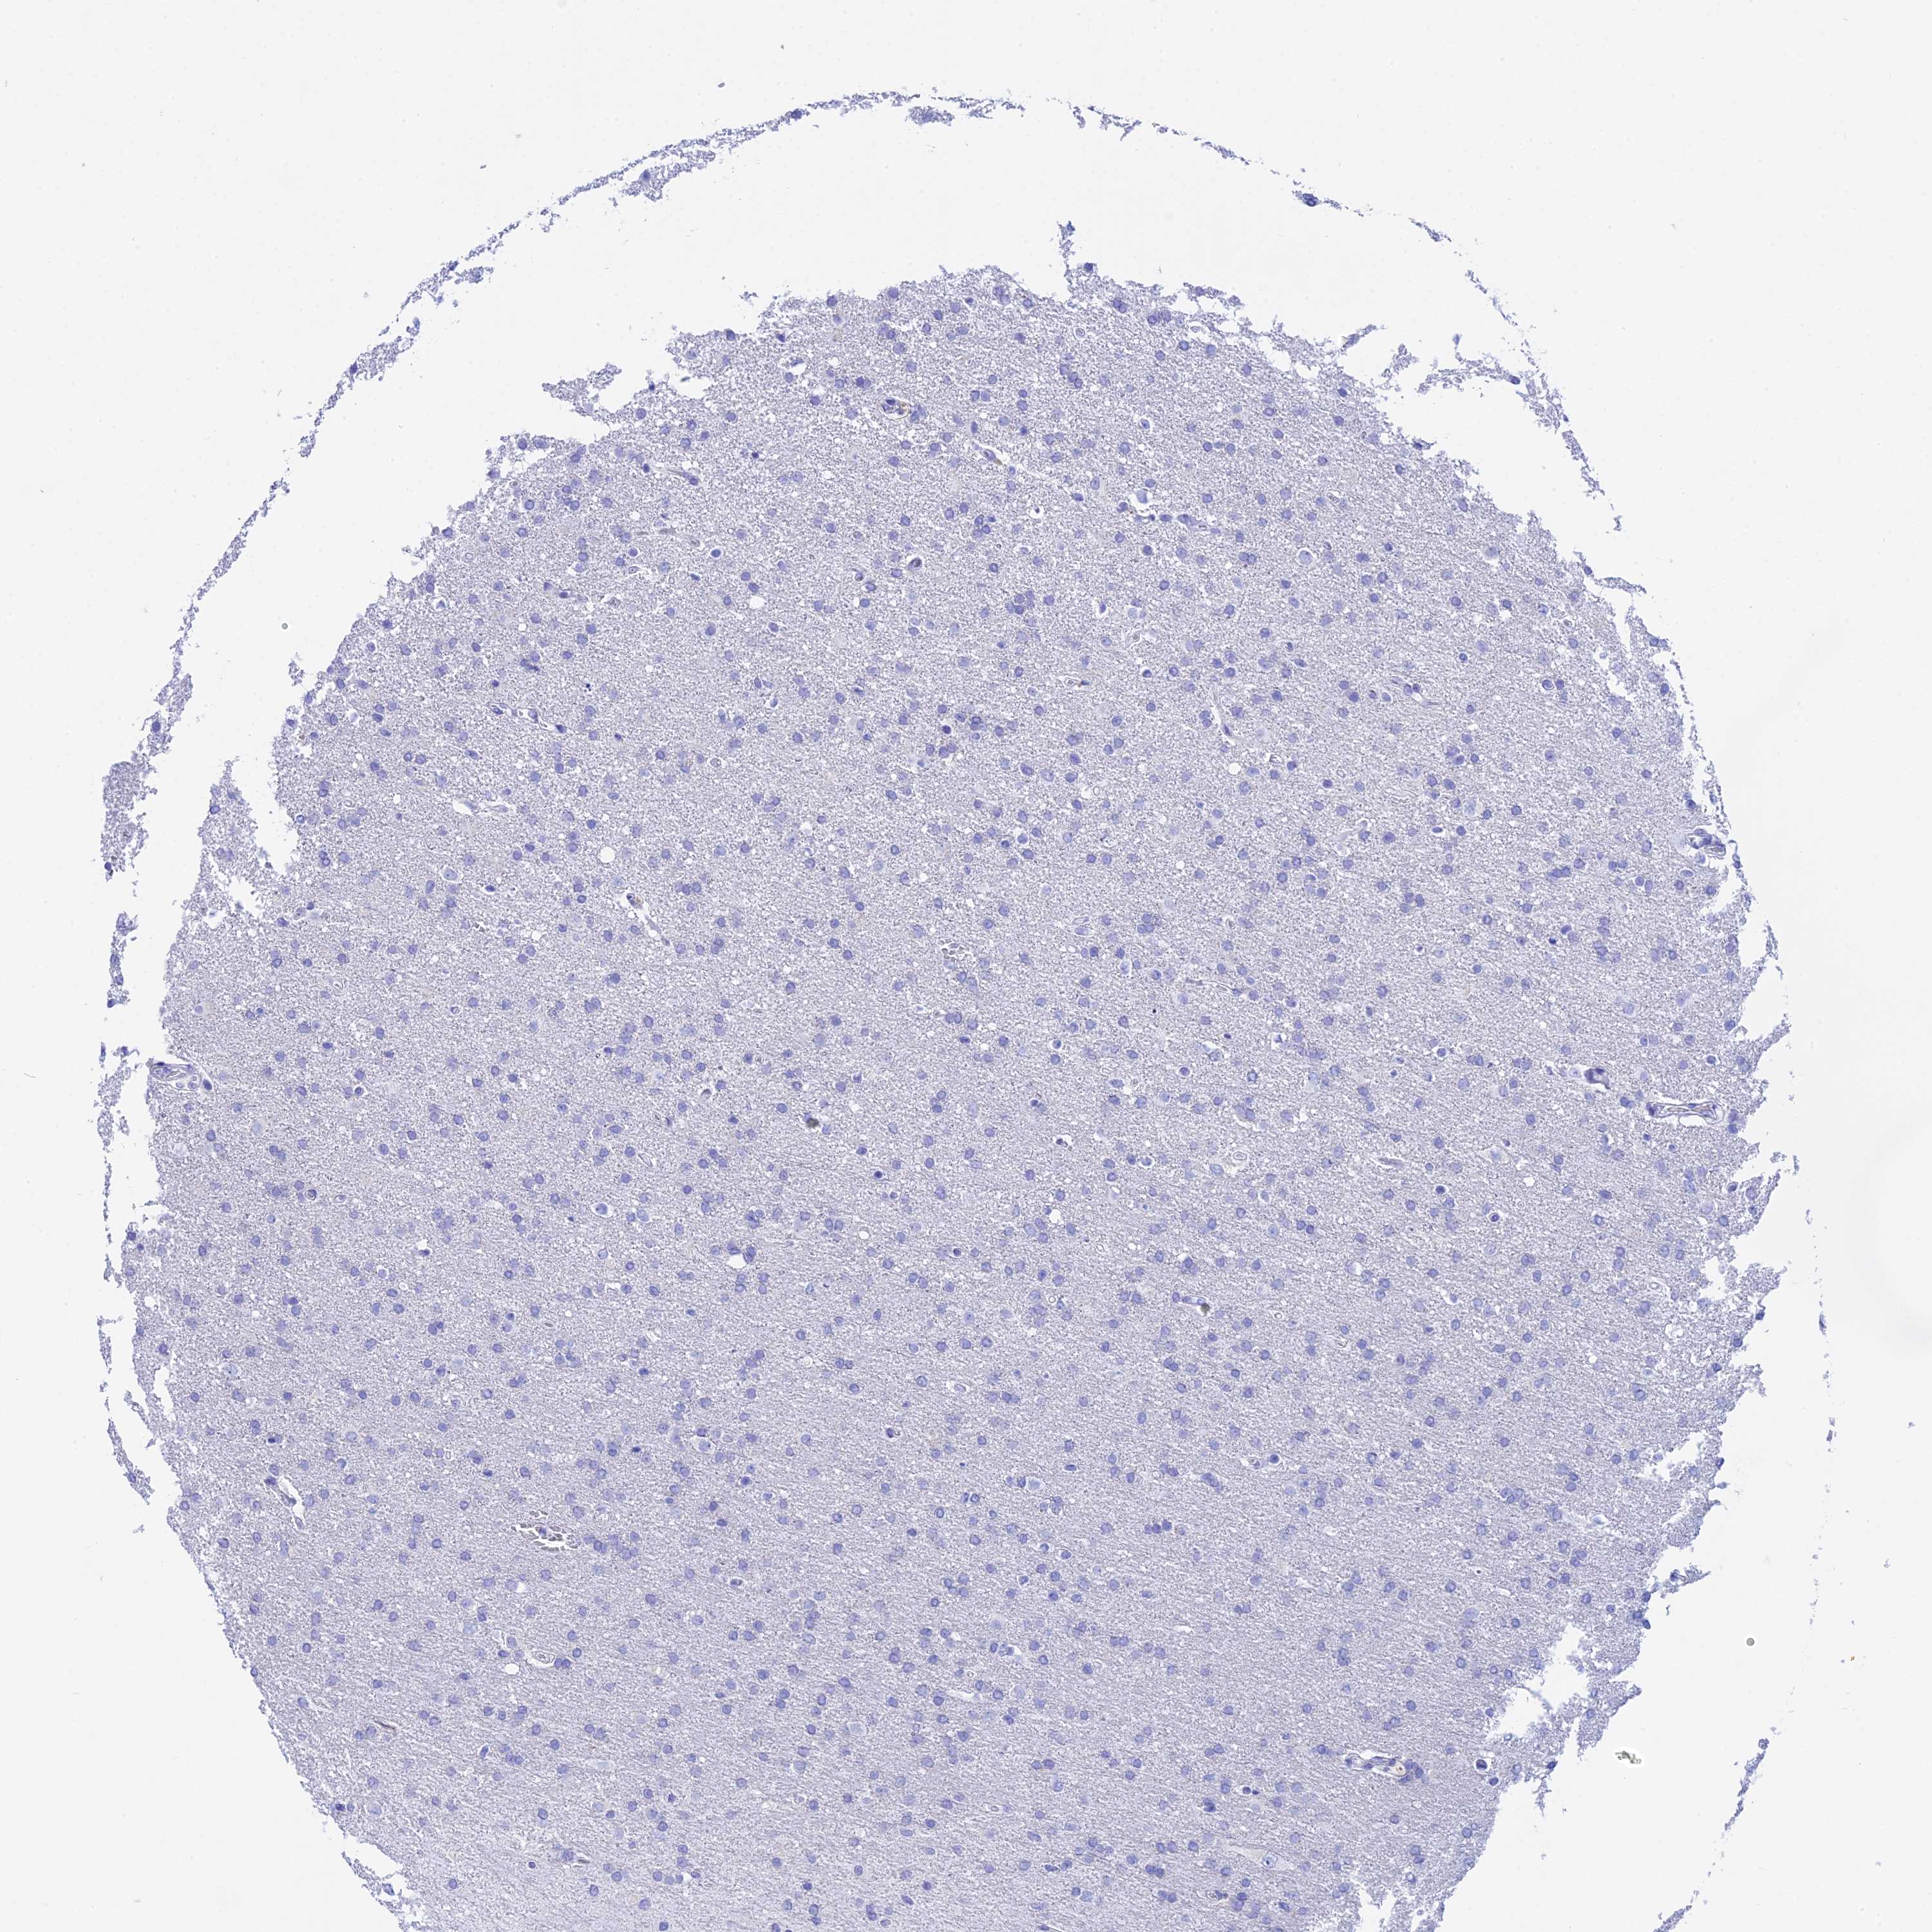

GLIOMA - Protein expressioni

A mouse-over function shows sample information and annotation data. Click on an image to view it in a full screen mode. Samples can be filtered based on level of antibody staining by selecting one or several of the following categories: high, medium, low and not detected. The assay and annotation is described here.

Note that samples used for immunohistochemistry by the Human Protein Atlas do not correspond to samples in the TCGA dataset.

Antibody stainingi

Antibody staining in the annotated cell types in the current human tissue is reported as not detected, low, medium, or high, based on conventional immunohistochemistry profiling in selected tissues. This score is based on the combination of the staining intensity and fraction of stained cells.

Each image is clickable and will lead to virtual microscopy that enables deeper exploration of all samples and also displays staining intensity scores, fraction scores and subcellular localization as well as patient and tissue information for each sample.

Antibody HPA041915

Antibody HPA042513

Staining

High

Medium

Low

Not detected

Intensity

Strong

Moderate

Weak

Negative

Quantity

>75%

75%-25%

<25%

None

Location

Nuclear

Cytoplasmic/membranous

Cytoplasmic/membranous,nuclear

Glioma, malignant, High grade

Glioma, malignant, Low grade